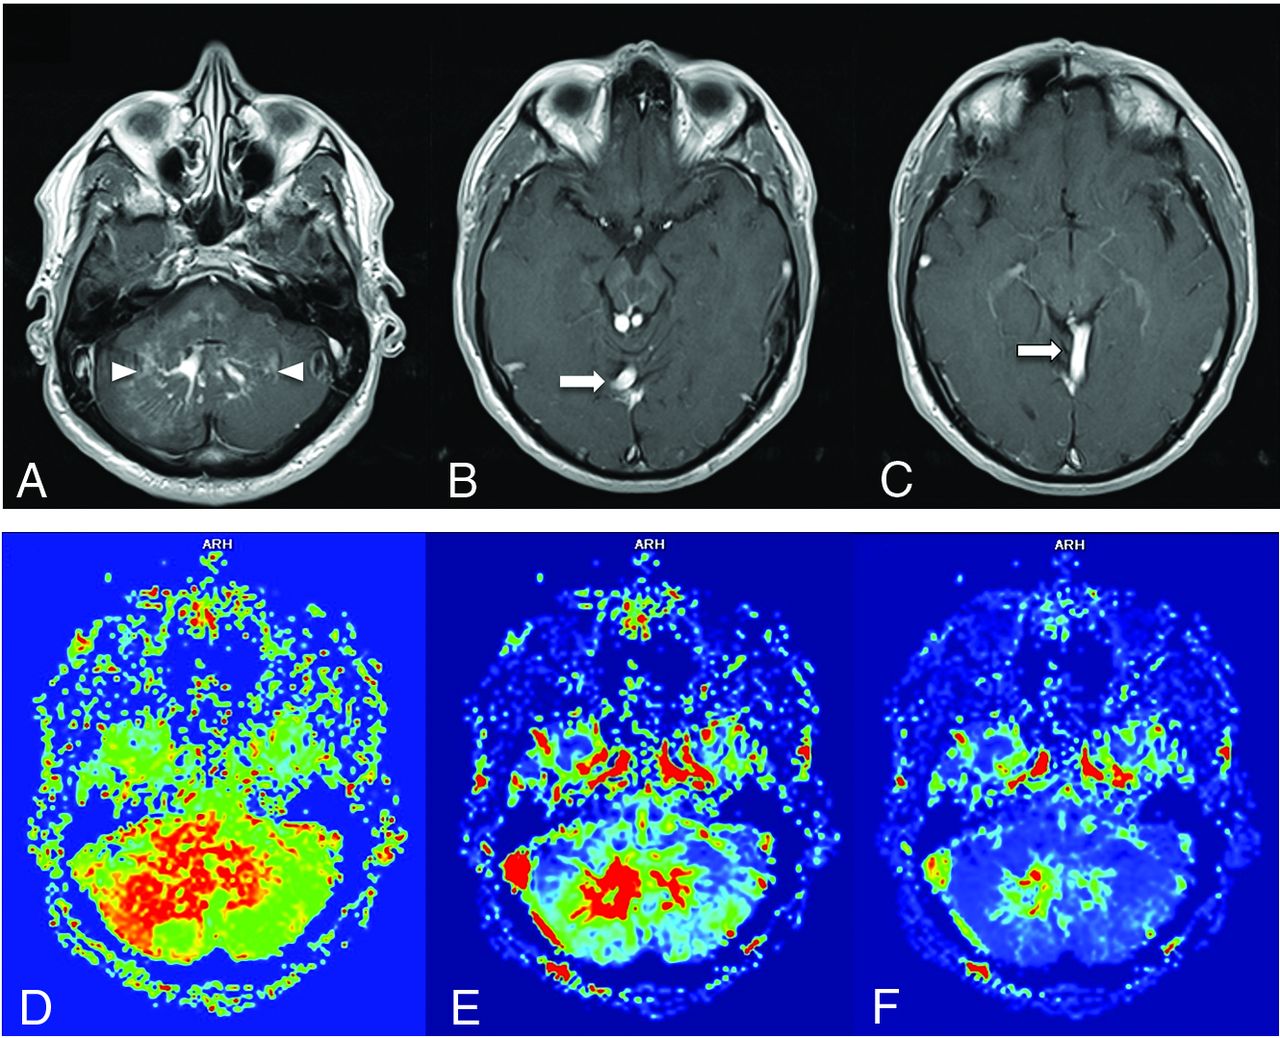

A patient with headache and ataxia. Contrast-enhanced T1WI (A–C) shows the DVA medusa veins in the cerebellar hemispheres (arrowheads) with a pair of draining veins and ultimately a common collector vein (arrows) draining into the right tentorial venous sinus. DSC MRI perfusion demonstrates a pronounced and asymmetrically increased MTT (D) in the right cerebellar hemisphere, consistent with venous hypertension. CBV (E) and CBF (F) images shows expected increased cerebral blood volume and flow in the DVA medusa veins.